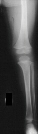

sensation on the dorsum of the foot, including the first web space. Radiographic

examination of the left knee revealed no osseous abnormalities (images

1 and 2). A fullness of the soft tissues was evident over the fibular head.